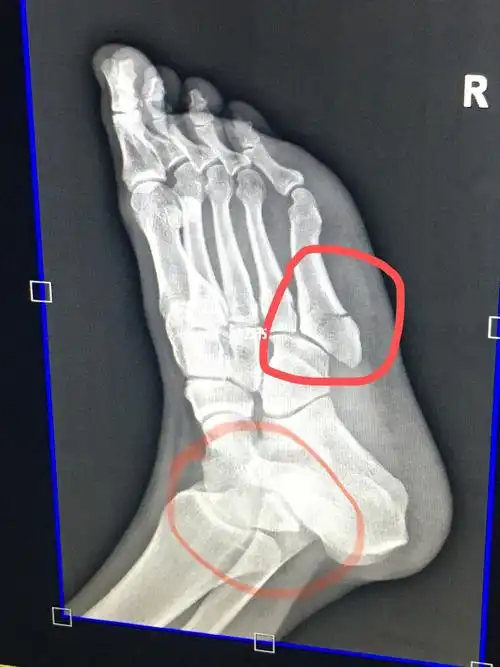

第五跖骨基底骨折40天复查 骨折40天了,还有一点缝,脱拐走路一星期

9月26日,踢球落地崴脚,第二天拍片发现第五跖骨骨折,打石膏38天了

左足第五跖骨基底部骨折

左脚第五跖骨骨折

第五跖骨骨折1个月 从2月13到3.14,骨折30天了,满一个月了.

x线诊断为左足第5跖骨基底部骨折,请问严重吗?如何尽快恢复?

我的右脚第五趾骨骨折记录 - 知乎